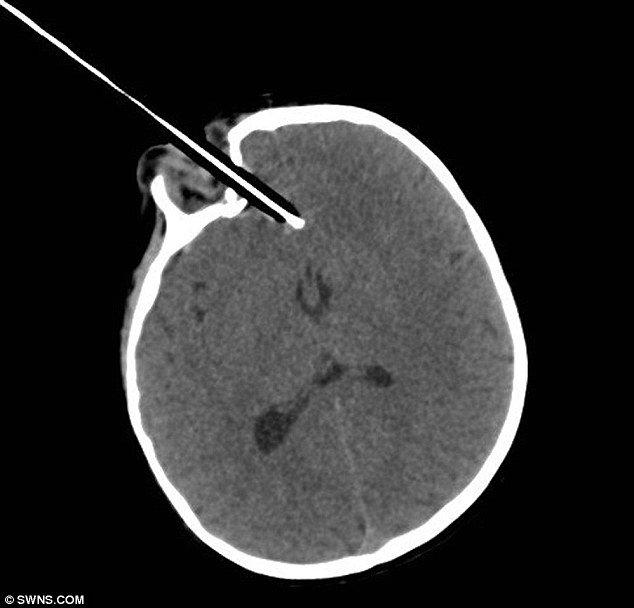

Οι ακτινογραφίες έδειξαν ότι το τραύμα ήταν πολύ σοβαρό και απαιτούνταν η παρέμβαση ενός ειδικού.

«Το μολύβι ήταν ένα χιλιοστό μακριά από το να χτυπήσει ένα μεγάλο αιμοφόρο αγγείο στον εγκέφαλο. Η μικρή ήταν πολύ τυχερή που γλίτωσε χωρίς μεγάλη αιμορραγία», ανέφερε ο νευροχειρουργός Ίαν Πόπλ.

Επίσης, σύμφωνα με τον Πόπλ το μολύβι δεν τραυμάτισε τον βολβό του ματιού.

Οι γιατροί έπρεπε να της αφαιρέσουν μέρος του κρανίου της για να μπορέσουν να κάνουν την επέμβαση.